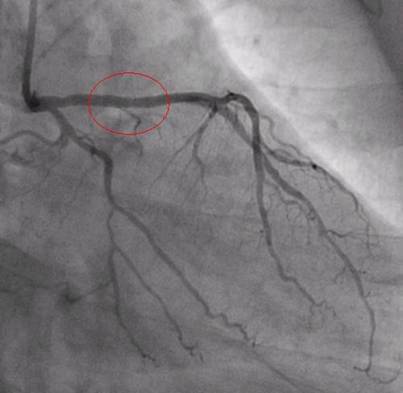

After reaching to the hospital, the doctors prescribed a test called angiogram. This test is basically to identify blood flow of heart arteries. When they finished the test they found a 94% block in the main artery, please see the image below with red circle.

At this point, I wanted to share my living style, which has caused this block in my heart arteries. Please see the below points of my life style, if any of these points are part of your life style then you are at risk, please change yourselves.